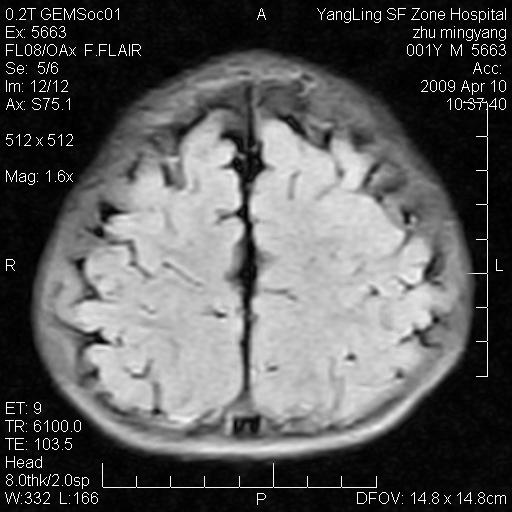

患者:1岁半,两天前外伤收住我院,ct检查小脑占位

考虑星形细胞瘤,建议增强

髓母细胞瘤或血管母细胞瘤,增强后可以鉴别;影像资料见 <。鱼博浪老师的《中枢神经系统ct与mr鉴别诊断》 小脑部肿瘤章节。

髓母细胞瘤或血管母细胞瘤!支持!

支持考虑髓母细胞瘤

考虑----髓母细胞瘤可能性大

考虑髓母细胞瘤或室管膜瘤。

支持髓母细胞瘤。

考虑髓母细胞瘤。

考虑髓母细胞瘤或星形细胞瘤

考虑髓母细胞瘤.

考虑髓母细胞瘤可能性大。

小脑肿瘤.考虑髓母细胞瘤可能.

就病灶部位及临床资料首先考虑髓母.